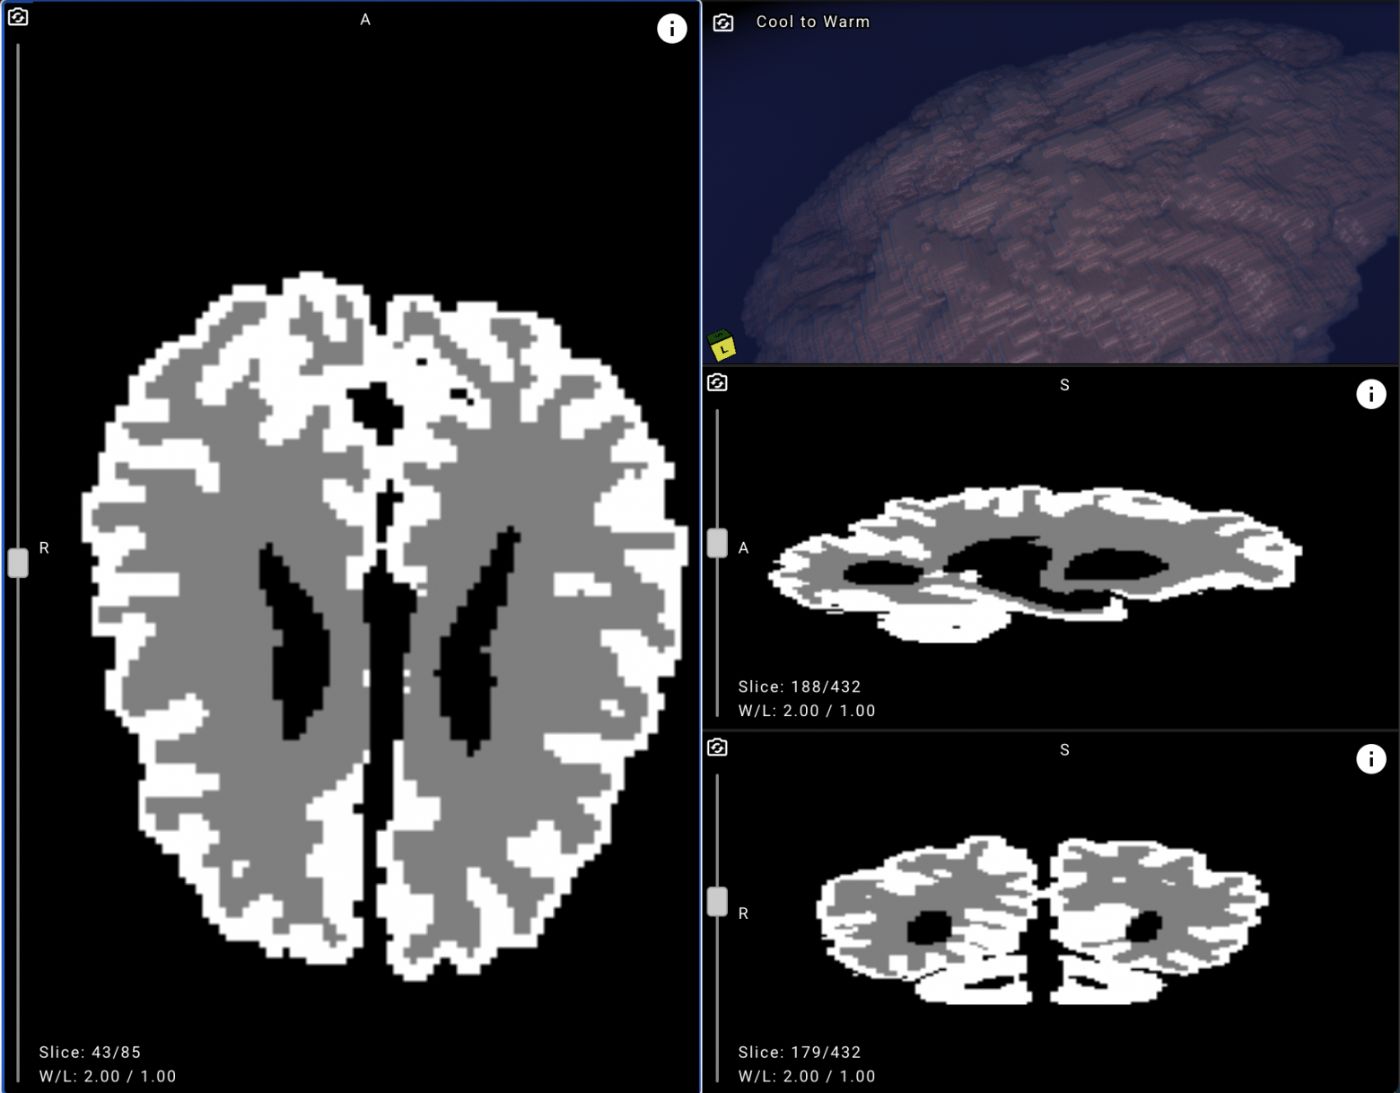

\n Let's look at the first stage.

\ Annotating the collected data. For patients over a year old, radiological brain images can be annotated using automated tools such as the open-source 3D Slicer, which calculates white matter and gray matter volumes. However, these methods are not effective for younger patients. On MRI scans of newborns, even seasoned radiologists may find it hard to distinguish white matter from gray matter, making annotation a meticulous, pixel-by-pixel task.

This cut the pre-annotation time for the entire dataset, making it possible to assess the algorithm's performance on it. According to our expert radiologists, pre-annotations were useful in 40% of cases, and that alone helped reduce the manual workload. Our ML specialists also benchmarked BIBSNet’s performance in segmenting gray matter (GM) and white matter (WM) on T1-weighted (sagittal) and T2-weighted (axial) MRI scans.

As a result, pre-annotation helped us build an annotated dataset of about 750 slices. This was enough to train and evaluate machine learning models for segmentation and detection. Before running the experiments, we split the dataset into training and validation sets, using the latter to check our metrics.

\ The Yandex School of Data Analysis team aimed to develop a segmentation model that could be as accurate as BIBSNet but deliver a much faster inference time.

To achieve this, the students ran a series of experiments on the iSeg-2019 dataset. For the neural network architectures, they examined U-Net, U-Net++, and DeepLabV3. For the feature extraction backbones, they tested ResNet-50, ResNet-101, ResNeXt-50, ResNeXt-101, and DenseNet-161.

Here's how the model performs on the validation set. Original study from the validation set:

\

Example output from the algorithm

Final metrics:

| \n | iou void | iou GM | iou WM | iou mean | |----|----|----|----|----| | unetresnext5032x4ddice1 | 0.981 | 0.629 | 0.501 | 0.703 |

The inference speed of the trained neural network running on a CPU is about 3 seconds.

The solution automatically identifies gray matter and white matter areas on each MRI slice, providing predictions with confidence scores.

The service is primarily morphometric, meaning it measures tissue volumes. Once processing is complete, users see the model's predicted volumes of gray matter, white matter, and cerebrospinal fluid, along with descriptions of the largest structures.

\ From the summary table, you can select a specific study to view the scan with the white matter and gray matter masks applied.